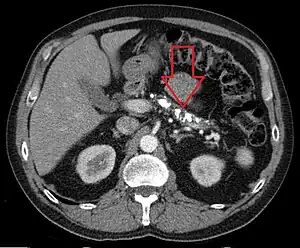

| Axial CT showing multiple calcifications in the pancreas in a patient with chronic pancreatitis | |

On CT scan, pancreatic and bile duct dilatation, atropy of pancreas, multiple calcifications of the pancreas, and enlargement of pancreatic glands can be found.[12]